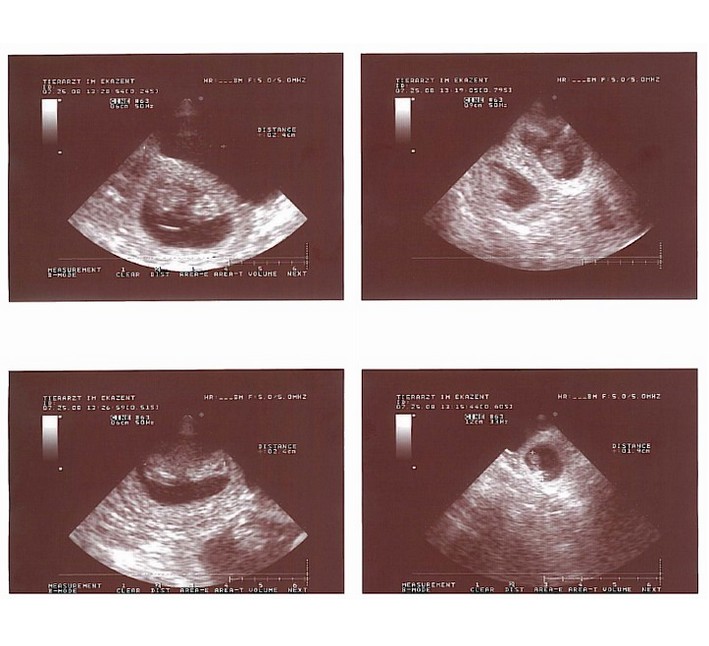

| Ultraschall / Sonography |

|

Emi pregnant |

N-Litter |